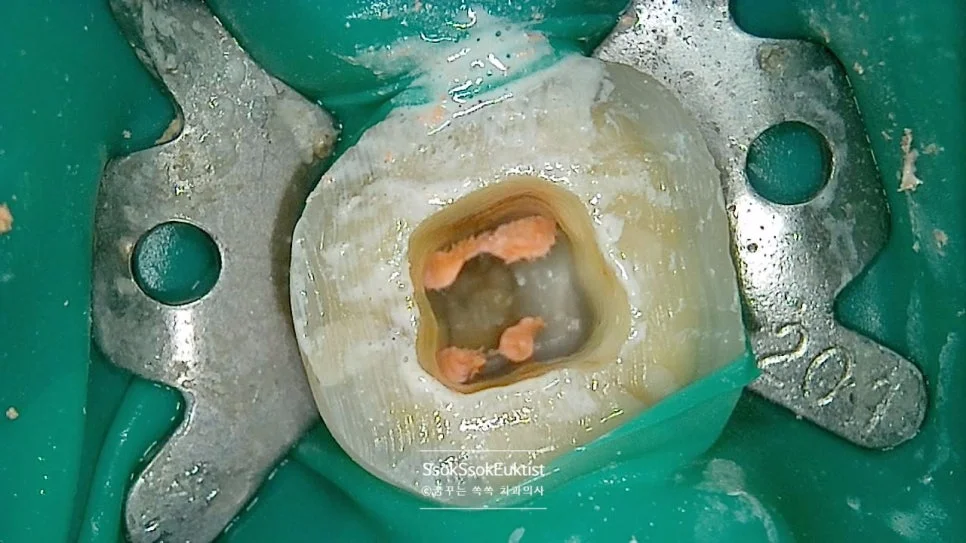

러버댐(초록색 고무 막) 격리 하에 신경치료 진행

신경치료의 마무리 후 촬영한 사진입니다.

여기서 보이는 초록색 고무 막을 사용하는 치과인가는 신경치료의 성공률에 지대한 영향을 주는 요소이기에, 이 고무 막을 사용하는 치과에서 신경치료받으시는 것을 추천드립니다!^^

대만의 517,234개 치아를 대상으로 한 대규모 연구에 따르면, 신경치료 시 러버댐을 사용한 경우 치료 후 발치 위험이 약 19% 감소하는 것으로 나타났습니다. 러버댐은 구강 내 세균이 치아 내부로 유입되는 것을 차단하여 신경치료의 장기 생존율을 높이는 핵심 요소입니다.

— Lin PY et al. (2014), Journal of Endodontics, 40(11):1733-1737

신경관 4개가 예쁘게 채워져 있는 것 같습니다. 실제 충전 후 X-ray를 보면 명확히 할 수 있는데요.